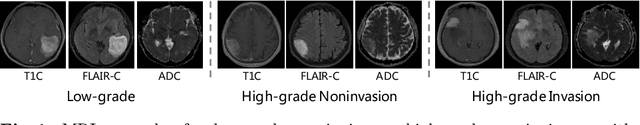

Abstract:Preoperative and noninvasive prediction of the meningioma grade is important in clinical practice, as it directly influences the clinical decision making. What's more, brain invasion in meningioma (i.e., the presence of tumor tissue within the adjacent brain tissue) is an independent criterion for the grading of meningioma and influences the treatment strategy. Although efforts have been reported to address these two tasks, most of them rely on hand-crafted features and there is no attempt to exploit the two prediction tasks simultaneously. In this paper, we propose a novel task-aware contrastive learning algorithm to jointly predict meningioma grade and brain invasion from multi-modal MRIs. Based on the basic multi-task learning framework, our key idea is to adopt contrastive learning strategy to disentangle the image features into task-specific features and task-common features, and explicitly leverage their inherent connections to improve feature representation for the two prediction tasks. In this retrospective study, an MRI dataset was collected, for which 800 patients (containing 148 high-grade, 62 invasion) were diagnosed with meningioma by pathological analysis. Experimental results show that the proposed algorithm outperforms alternative multi-task learning methods, achieving AUCs of 0:8870 and 0:9787 for the prediction of meningioma grade and brain invasion, respectively. The code is available at https://github.com/IsDling/predictTCL.